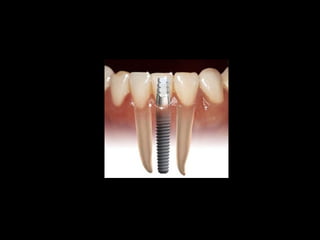

Definición de Oseointegración

• Branemark:

Es la unión íntima entre tejido óseo vivo y

ordenado y la superficie del implante,

sometido a carga funcional.

• Leckholm y Espósito:

Es la ausencia de dolor y movilidad de los

implantes bajo carga funcional